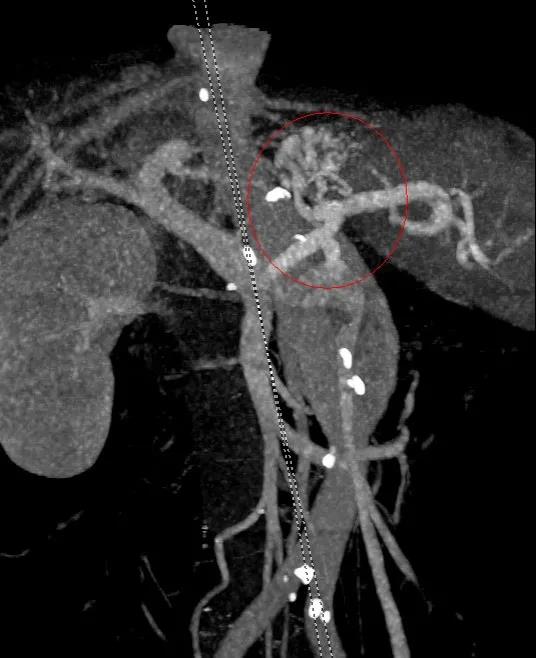

入院后予禁食、抑酸、補液、輸血處理,與家屬溝通,完善胃鏡檢查,結(jié)果示胃底巨大曲張靜脈團、門脈高壓性胃病。蓋偉主任考慮胃底靜脈團大、靜脈壓力高,合并分流道的可能性越大,且多數(shù)為胃脾分流,應首先完善門靜脈血管成像檢查,以明確血管情況。成像檢查結(jié)果符合食管胃底靜脈曲張CT表現(xiàn),胃底血管部分與脾靜脈相交通。

科室組織術前討論,共同讀片,分析:該患者巨大胃底靜脈曲張存在胃脾分流道,巨大者難以套扎,常規(guī)組織膠血管內(nèi)注射治療易引起異位栓塞。術前CT門脈成像檢查清晰顯示靜脈團的血管走行及血管的出入口大致在胃底的位置,鈦夾夾閉可以先行阻斷或減緩血流,隨后的組織膠治療不易發(fā)生異位栓塞。于是,團隊決定采用目前最新的鈦夾限流聯(lián)合組織膠栓塞術處理該患者的胃底曲張靜脈。

術前胃鏡及血管成像